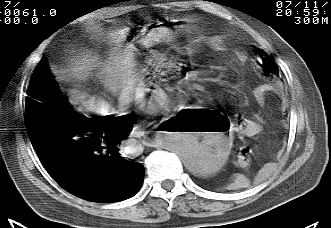

标题: CT10753:女, 64岁 隔疝 [打印本页]

标题: CT10753:女, 64岁 隔疝

女, 64岁 三十年前胸部外伤史, 间断胸闷,

典型左侧膈疝,疝出物为胃和大网膜,纵隔右移

同意左侧膈疝,不过,有过外伤史,左肺有受压征象,同时有胸膜增厚。

左侧隔疝(创伤性?),与外伤关系大。